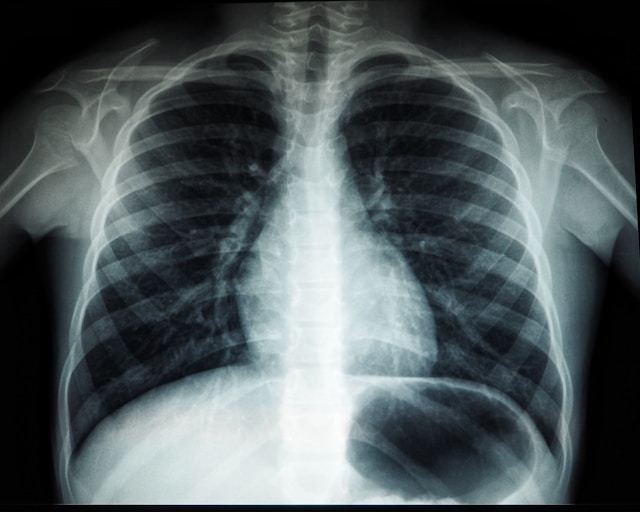

한국을 포함한 동아시아에서는 신규 폐암 환자의 절반 이상이 비흡연자로 보고되고 있다. 따라서 흡연력 기준만으로는 폐암 발병 위험을 예측하고 데 한계가 있다는 지적이 제기돼 왔다.

흡연 경험이 없더라도 만성 폐질환 병력이 있는 경우 폐암 발병 위험이 3배 가까이 증가하는 것으로 나타났다.

삼성서울병원은 이 병원 폐식도외과 김홍관·이정희 교수와 서울아산병원 호흡기내과 지원준 교수가 이끄는 연구팀은 2016∼2020년 삼성서울병원과 서울아산병원에서 비소세포폐암을 진단받은 3천명과 폐에 이상이 없는 대조군 3천 명을 선정해 위험 요인을 정밀 분석했다. 양 집단은 모두 흡연 경험이 없는 비흡연자였다.

그 결과 비흡연자 폐암 발병의 가장 강력한 위험인자는 ‘만성 폐질환 유무’인 것으로 나타났다. 비흡연 환자 중에서 폐결핵 등 폐 관련 질환 병력이 있는 경우 폐암 발병 위험이 대조군보다 2.91배 높았다.

특히 만성폐쇄성폐질환(COPD) 환자의 경우 폐암에 걸릴 위험이 7.26배까지 올라갔다. 연구진은 폐에서 계속되는 만성적 염증 반응 때문일 것으로 추정했다.